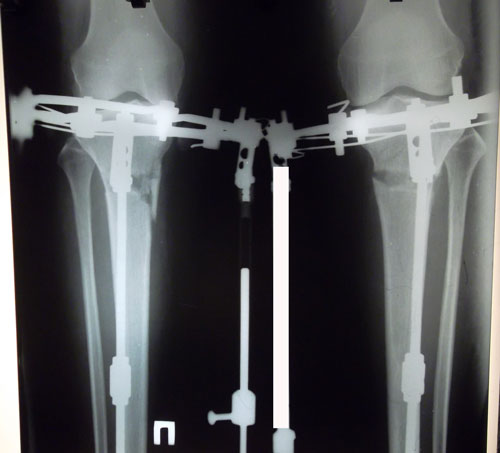

30 дней с момента операции.

РЕНТГЕН НА 30 - ЫЙ ДЕНЬ С МОМЕНТА ОПЕРАЦИИ.

РЕНТГЕН ДО ОПЕРАЦИИ